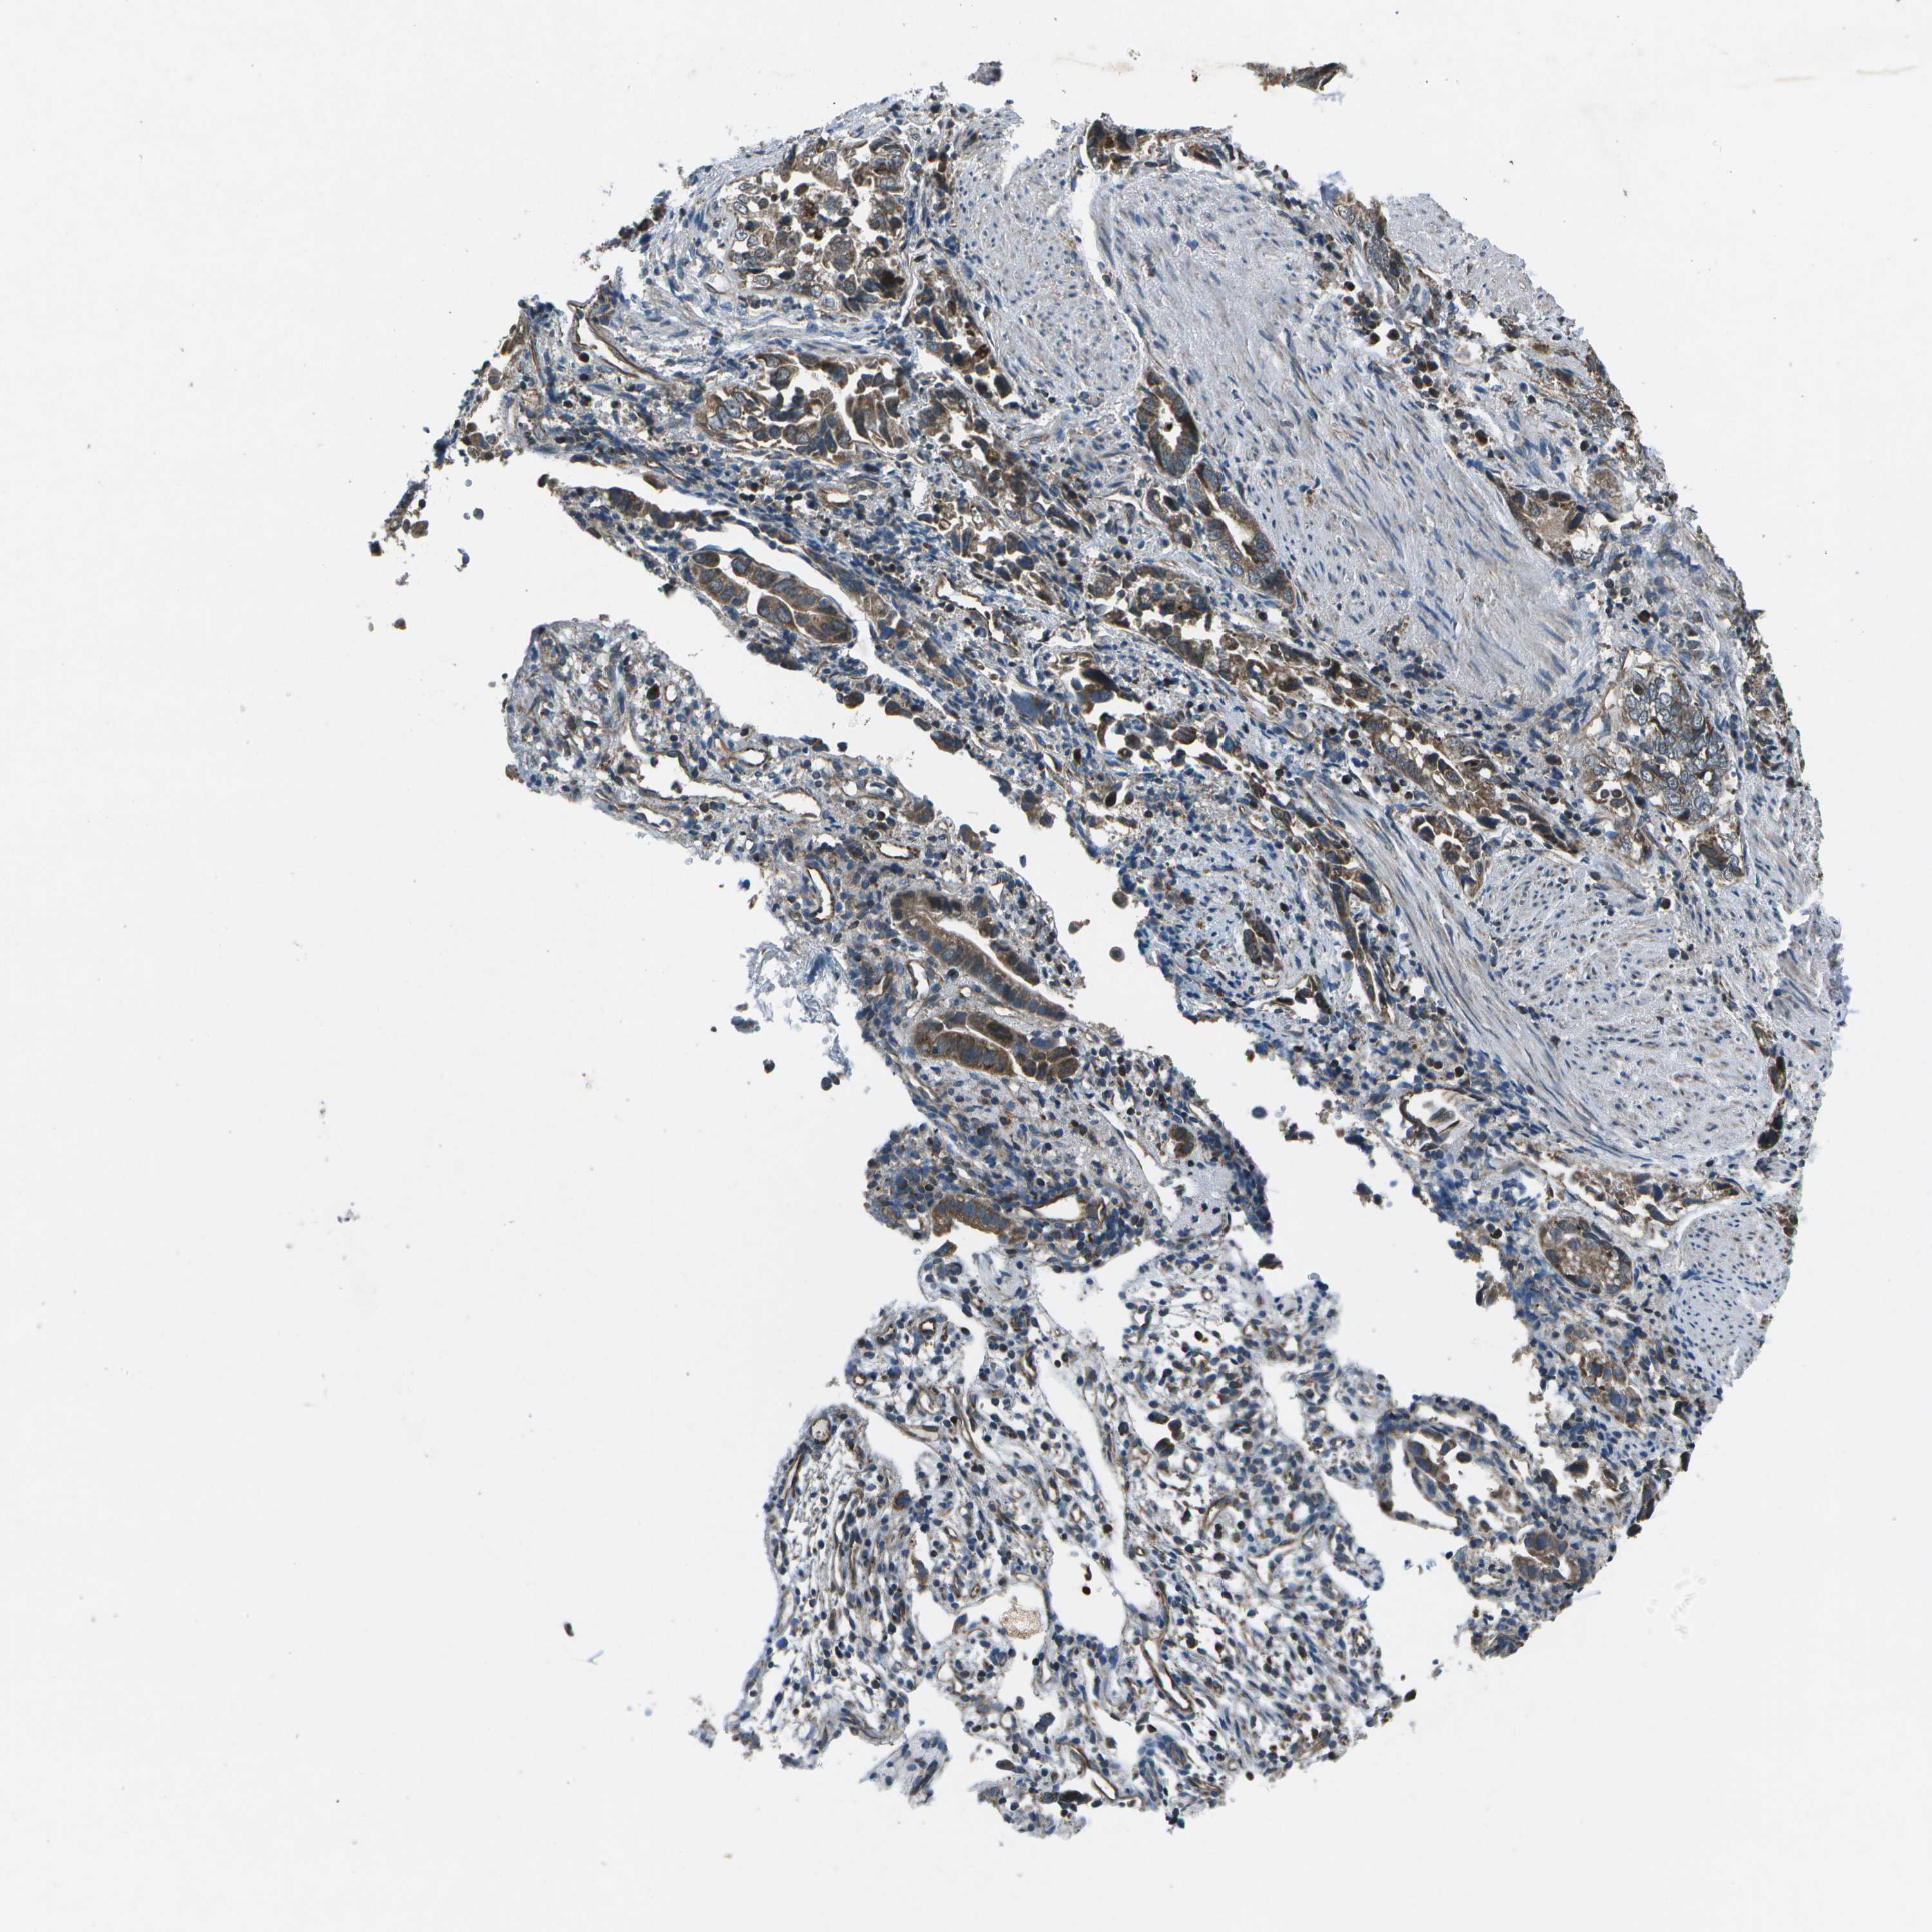

LIVER CANCER - Protein expressioni

A mouse-over function shows sample information and annotation data. Click on an image to view it in a full screen mode. Samples can be filtered based on level of antibody staining by selecting one or several of the following categories: high, medium, low and not detected. The assay and annotation is described here.

Note that samples used for immunohistochemistry by the Human Protein Atlas do not correspond to samples in the TCGA dataset.

Antibody stainingi

Antibody staining in the annotated cell types in the current human tissue is reported as not detected, low, medium, or high, based on conventional immunohistochemistry profiling in selected tissues. This score is based on the combination of the staining intensity and fraction of stained cells.

Each image is clickable and will lead to virtual microscopy that enables deeper exploration of all samples and also displays staining intensity scores, fraction scores and subcellular localization as well as patient and tissue information for each sample.

Antibody HPA016496

Antibody CAB022082

Staining

High

Medium

Low

Not detected

Intensity

Strong

Moderate

Weak

Negative

Quantity

>75%

75%-25%

<25%

None

Location

Nuclear

Cytoplasmic/membranous

Cytoplasmic/membranous,nuclear

Cholangiocarcinoma

Carcinoma, Hepatocellular, NOS